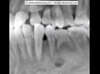

Canine incluse (panoramique)

Canine incluse